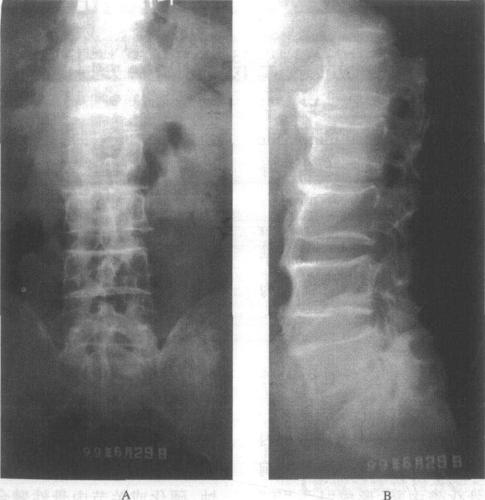

弥漫性特发性骨质增生症

腰椎骨质增生.png

腰椎骨质增生